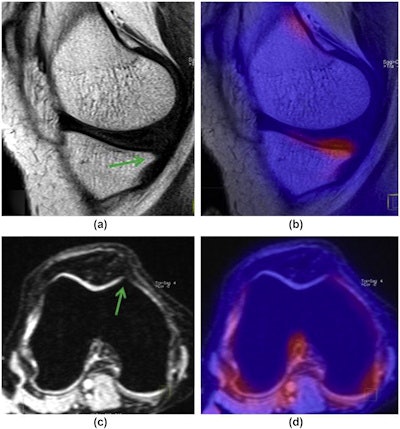

In this study, the researchers aimed to show that PET/MRI can identify compartmental differences between bone marrow lesions and osteophytes in the knees of osteoarthritis patients based on metabolic uptake values of F-18 Sodium Fluoride (NaF), a known marker of bone remodeling.

Images of both knees were acquired on a PET/MRI system (Biograph mMR, Siemens Healthineers) and analyzed by a musculoskeletal radiologist and a nuclear medicine physician, both with more than 15 years of experience. Bone marrow lesions and osteophytes were scored using MRI Osteoarthritis Knee Score (MOAKS) criteria and corresponding maximum standardized uptake (SUVmax) values.

In the 32 knee joints analyzed, 53 bone marrow lesions and 177 osteophytes were identified. Bone marrow lesions and osteophytes both showed statistically significant differences among knee compartments, with SUVmax for bone marrow lesions and osteophytes highest in the medial tibia (MT).

In addition, the mean SUVmax increased with the grade of bone marrow lesions, from 2.7 for grade 1 lesions up to 48.5 for grade 3 lesions. SUVmax was highest in lesions in the MT, followed by those identified in the patella, medial femoral condyle, trochlea (Troc), lateral patellar facet-medial patellofemoral ligament (LPF-MPF), and the lateral collateral ligament (LT).

Similar to the bone marrow lesions, a proportional increase in SUVmax was also observed depending on the size of osteophytes, ranging from 1.3 for grade 1 osteophytes up to 6.64 for grade 3 osteophytes. SUVmax was highest in osteophytes in the MT, followed by those in the LPF, MPF, patella, LT, and Troc.

"F-18 NaF-PET/MRI showed that [bone marrow lesions] and osteophytes had different uptake values due to bone remodeling among the various knee compartments," the researchers stated.